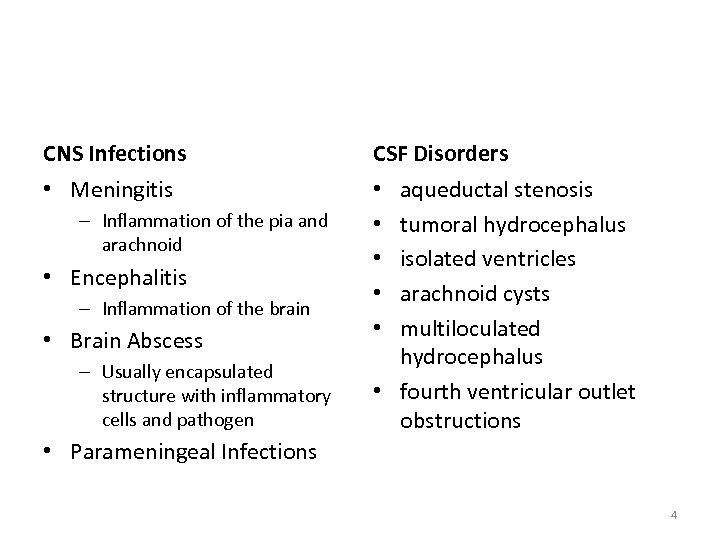

CNS Infections CSF Disorders • Meningitis • • • – Inflammation of the pia and arachnoid • Encephalitis – Inflammation of the brain • Brain Abscess – Usually encapsulated structure with inflammatory cells and pathogen aqueductal stenosis tumoral hydrocephalus isolated ventricles arachnoid cysts multiloculated hydrocephalus • fourth ventricular outlet obstructions • Parameningeal Infections 4